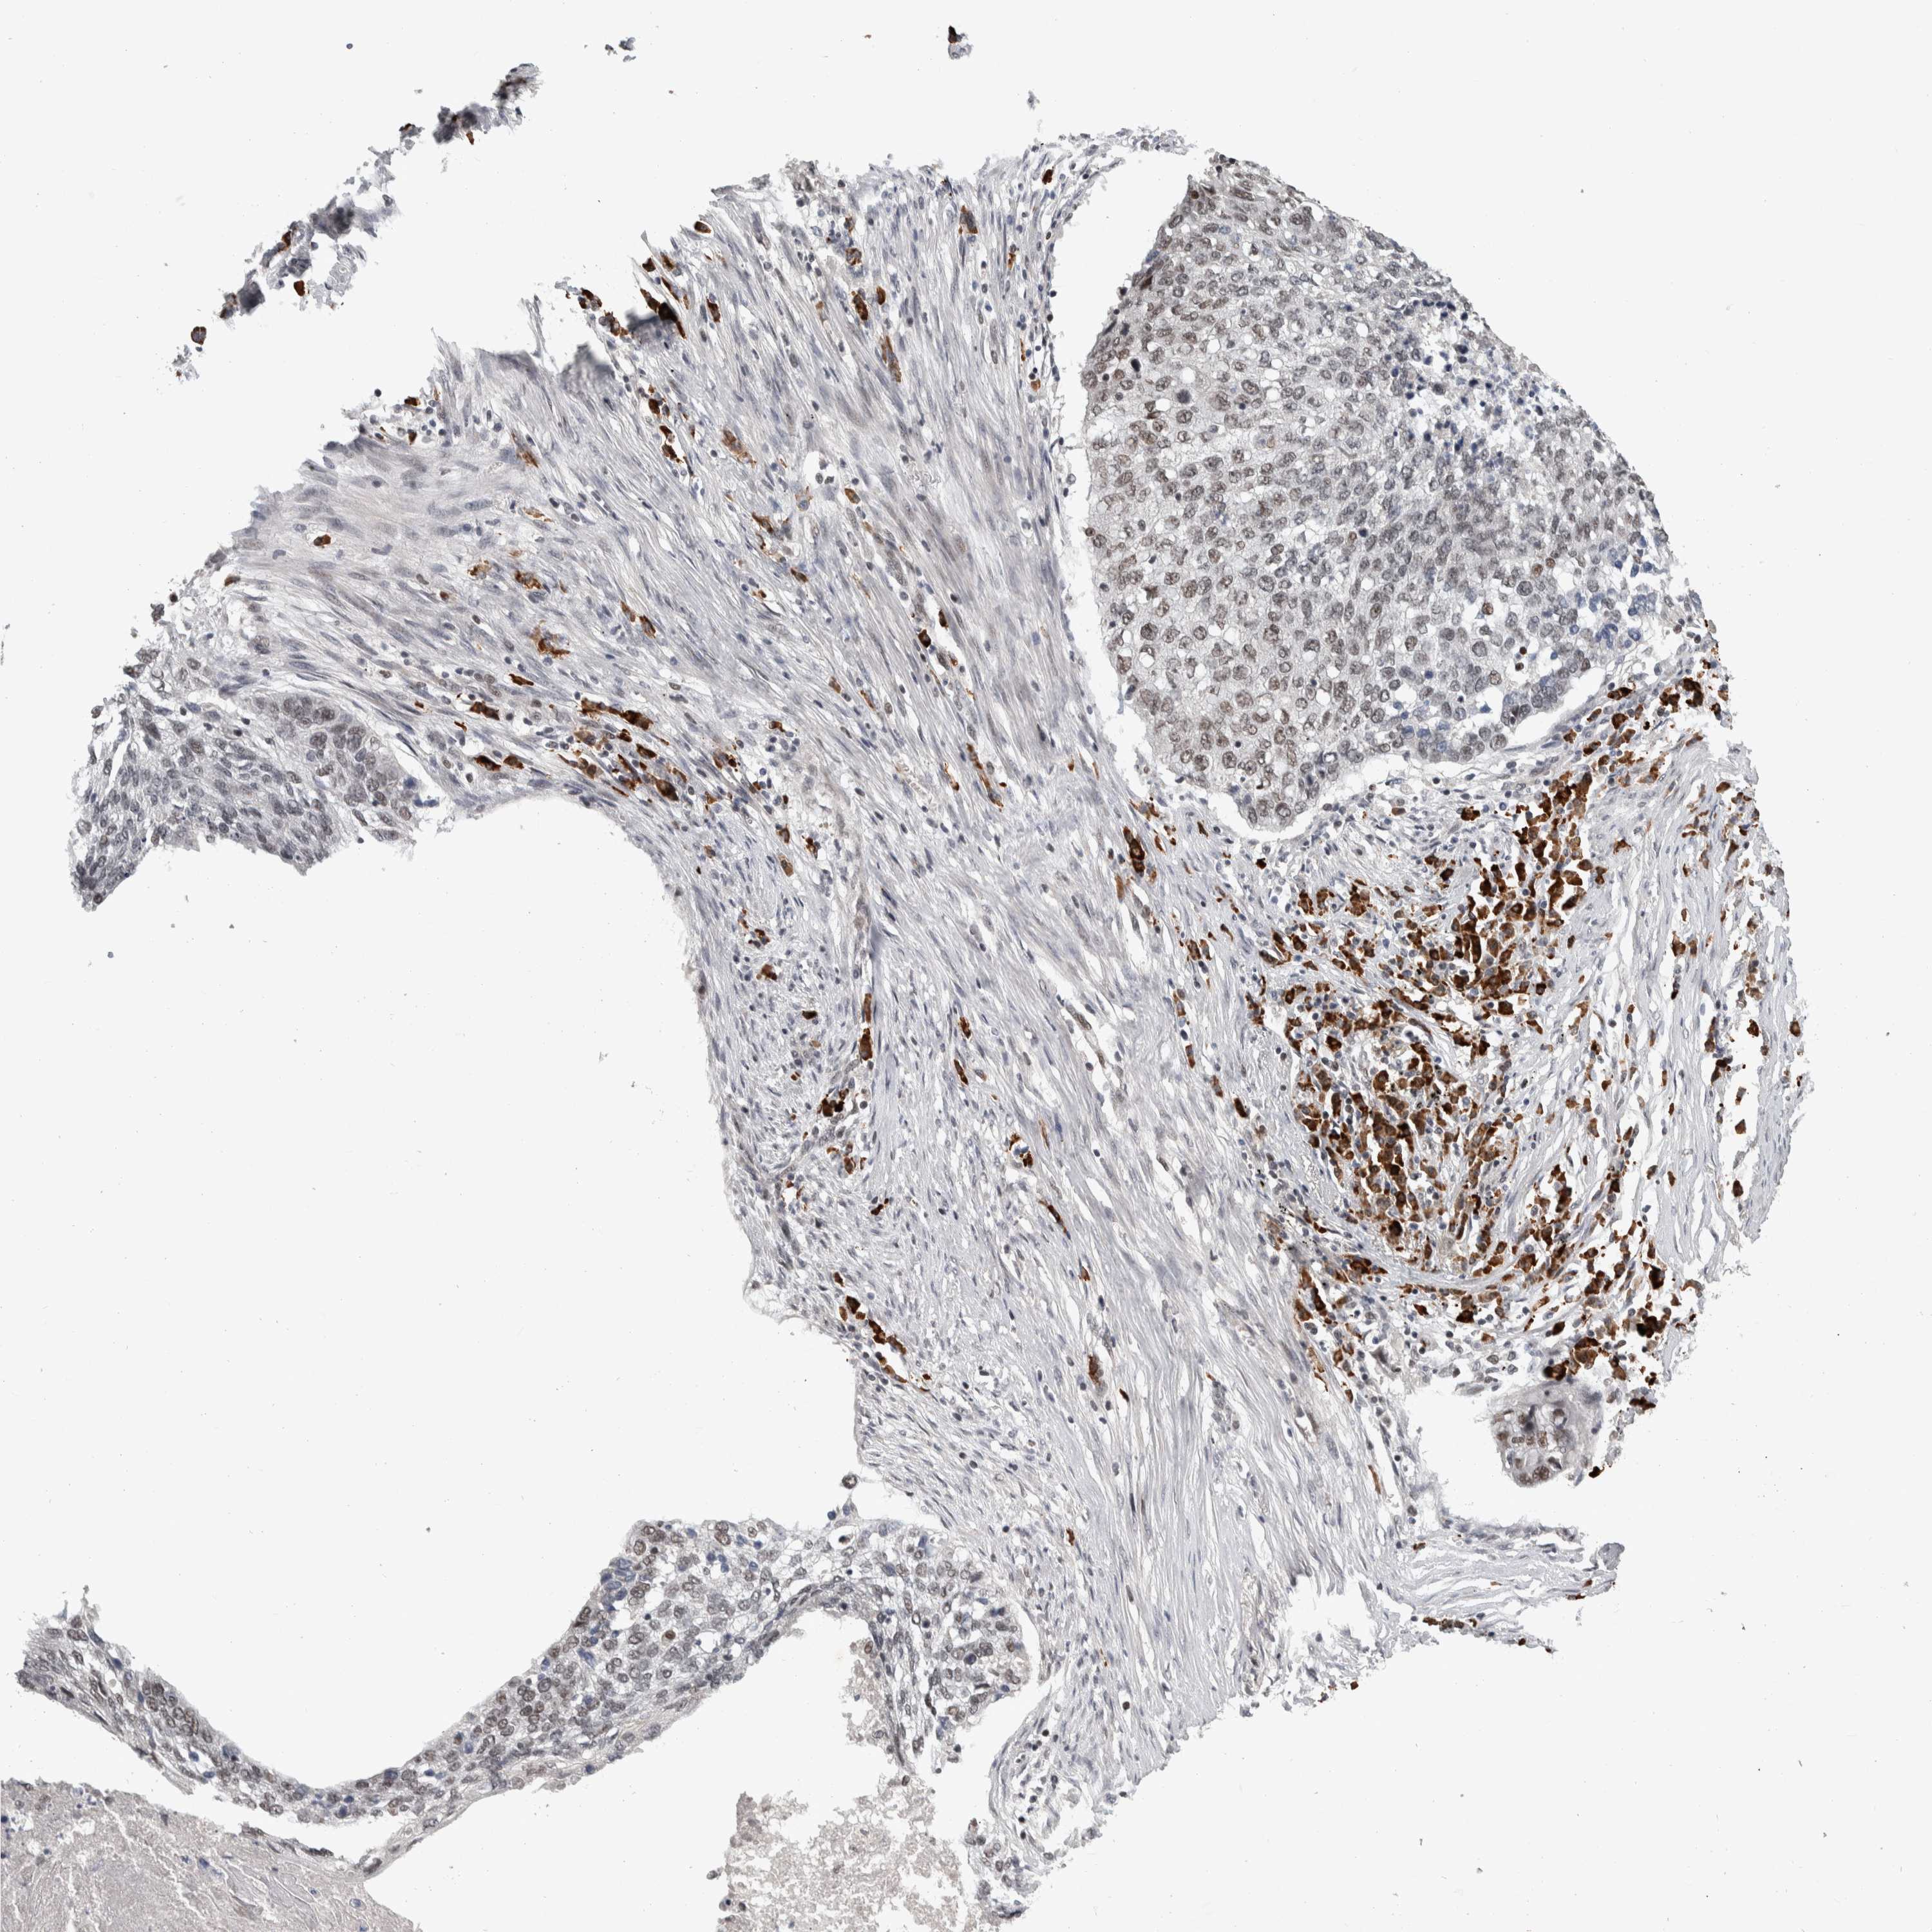

CANCER LUNG CANCER Show tissue menu

LUAD TCGA LUAD VALIDATION LUSC TCGA LUSC VALIDATION PROTEIN LUAD CPTAC PROTEIN LUSC CPTAC PROTEIN EXPRESSION

Lung cancer

Human cancer

Lung adenocarcinoma

Lung squamous cell carcinoma